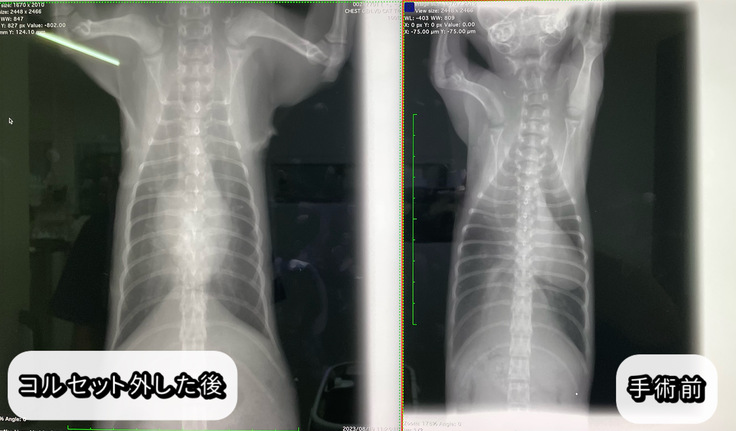

レントゲンの写真を載せておきます。

↑心臓の位置も横隔膜の形も

手術前に比べてすごく綺麗になりました。